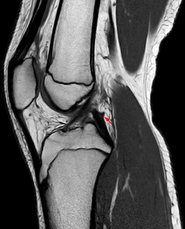

Posterior meniscofemoral ligament on MRI, sagittal

The Posterior meniscofemoral ligament is a small fibrous band of the knee joint. It attaches to the posterior area of the lateral meniscus and crosses superiorly and medially behind the posterior cruciate ligament to attach to the medial condyle of the femur.

Posterior meniscofemoral ligament (Wrisberg) behind the posterior horn of the lateral meniscus close to its insertion. Sometimes wrongly interpreted as a meniscal tear.